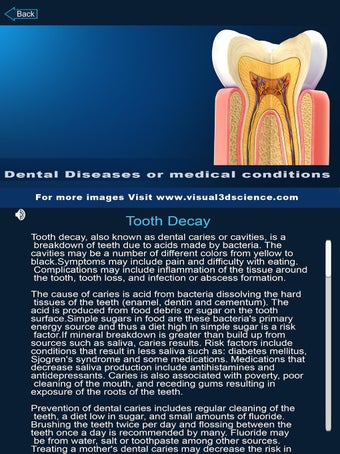

Esta aplicación es un modelo 3D de los dientes, que contiene muchas partes y muestra las condiciones dentales. Cada parte tiene un nombre y una función. Puedes mover la cámara alrededor del modelo para obtener una vista de 360° de las diferentes partes. Puedes hacer zoom para ver mejor cada parte. También puedes rotar la cámara para obtener una vista diferente del modelo.